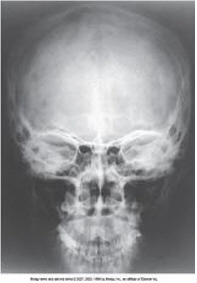

PA axial Caldwell

parietoacanthial (waters)

waters

parietoacanthial (modified waters)